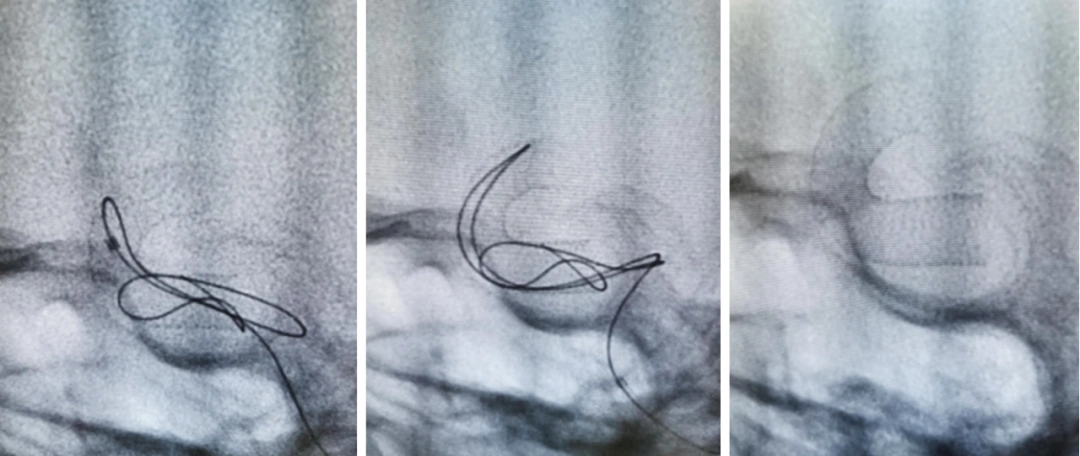

7月31日,中山一院齐铁伟主任一巨大动脉瘤使用tunbridge支架tb4545

卒中小组讨论后决定立即进行覆膜支架置入术,重建血管壁,隔绝动脉瘤